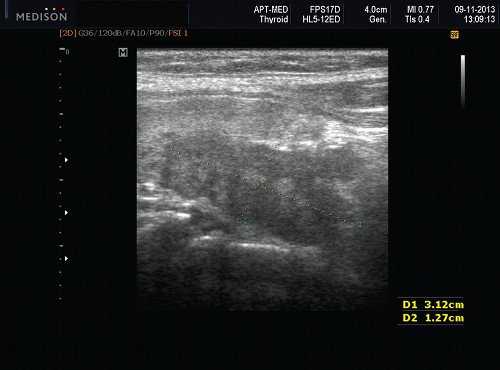

- УЗИ щитовидной железы. Эхоскопическая картина аномалий может быть различной. При агенезии железа не определяется в типичном месте. При гипоплазии тиреоидный объем уменьшен, паренхима диспластична. Гемиагенезия диагностируется по наличию единственной доли ЩЖ, отсутствию перешейка. При аномалиях положения железы тиреоидная ткань обнаруживается в других анатомических областях. УЗИ используется для проведения тонкоигольной биопсии и морфологического подтверждения диагноза.